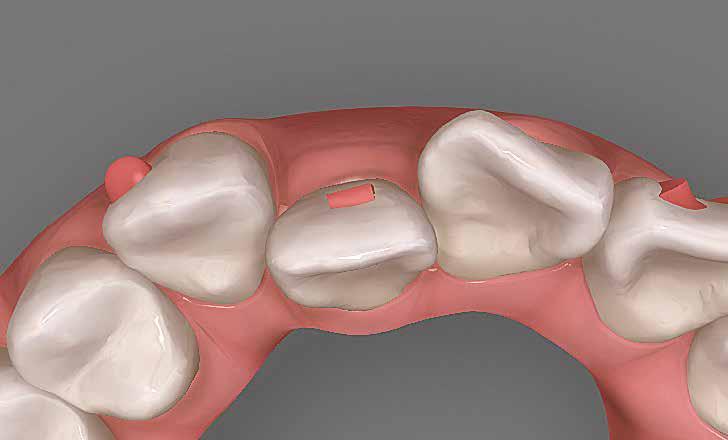

A hiányzó oldalsó kismetszők részárással történő kezelése során a szemfogak és oldalsó fogak meziális mozgatása közben a fogszabályozó orvosnak csiszolással kell a fogak formáját igazítani. Már a kezelés elejétől a szemfog elcsiszolása nem csak az incizális részre kell hogy kiterjedjen, hanem az approximális, palatinális és a vesztibuláris felszín éli negyedére is. Így érhetünk el egy rövidebb klinikai koronát, a vesztibulo-orális méret csökkenését, egy incizális élet, valamint a szemfog megfelelő pozicionálását a kismetsző helyén. A túl széles szemfog megakadályozza a megfelelő interkuszpidáció kialakítását az oldalzónában. A palatinális felszín elcsiszolásával biztosítjuk az interferenciák nélküli metszővezetést, és a megfelelő overjetet a frontfogak enyhe érintkezésével. Ha a szemfogra a későbbiekben esztétikai pótlás készül, a megfelelő approximális elcsiszolás (az esztétikai fogorvossal történő egyeztetés után) biztosítja a zenith kívánatos pozícióját a későbbi felépítéshez. A mezializált kisőrlő palatinális csücskének elcsiszolására csak akkor van szükség, ha ez akadályozza a megfelelő fogérintkezést. Az első kisőrlő mindkét csücske fontos a már a szemfog helyén álló fog esztétikai és funkcionális beállításához.

A szemfog oldalsó kismetsző helyére történő bemozgatása során a fog átalakítása javasolt a két fog eltérő morfológiai adottságai miatt (1. a-b. ábra). A fog kontúrozása, vagy úgynevezett formázása magába foglalja az approximális felszínek elcsiszolását, valamint a többi fogfelszín igazítását a kívánt fogformának megfelelően [1].

1. Tervezés

Már a kezelési tervezés fázisában meg kell határozni a zománc elcsiszolásának pontos mértékét az egyes fogak esetében [18]. Szemfog oldalsó metszővé való átalakítása során az aranymetszés szabályait vesszük alapul [19-22], vagy készíthetünk egy wax-upot. A beavatkozást megelőzően meg kell határozzuk a kívánt korona magasságát, azaz, hogy mennyit kell elcsiszolni a szemfog csücskéből, és milyen kiterjedésű felépítményre lesz szükség az incizális él kialakításához. Az optimális mezio-disztális szélesség kialakításával egyrészt elegendő helyet biztosítunk a kisőrlő megfelelő pozicionálásához a szemfog helyén az okklúziós kulcsnak megfelelően, valamint a szükséges felépítésekhez.

2. Interproximális területek hozzáférhetősége Az approximális felszínek elcsiszolása előtt fontos kialakítani a megfelelő kontaktpontokat, ehhez pedig ki kell nivellálni a fogívet, és meg kell oldani a rotációkat [23]. Ugyanakkor fontos a zenith ideális magassága és megfelelő angulációja. Az esztétikus fogorvos a fogkorona anatómiája és a zenith pozíciója alapján határozza meg a meziális és disztális felszínek elcsiszolásának mértékét. Mivel a középső metsző és a szemfog közötti kontaktpont nem ideális, ezért a szemfog tengelyét úgy kell beállítani, hogy az elcsiszolásokat követően a lehető legjobb érintkezést hozzuk létre a két fog között.

Szemfog mezializációt követően történik az approximális felszínek igazítása. Elérjük a megfelelő mezio-disztális szélességet, és a kontaktpont incizális irányba helyeződik át. Ebben a fázisban mindig szükséges egyeztetni az esztétikai pótlást készítő fogorvossal a szükséges szemfogformáról és a későbbi felépítmény pontos helyzetéről. Az esztétikai fogorvosnak kell eldöntenie a meziális és disztális felszínek elcsiszolásának mértékét is.